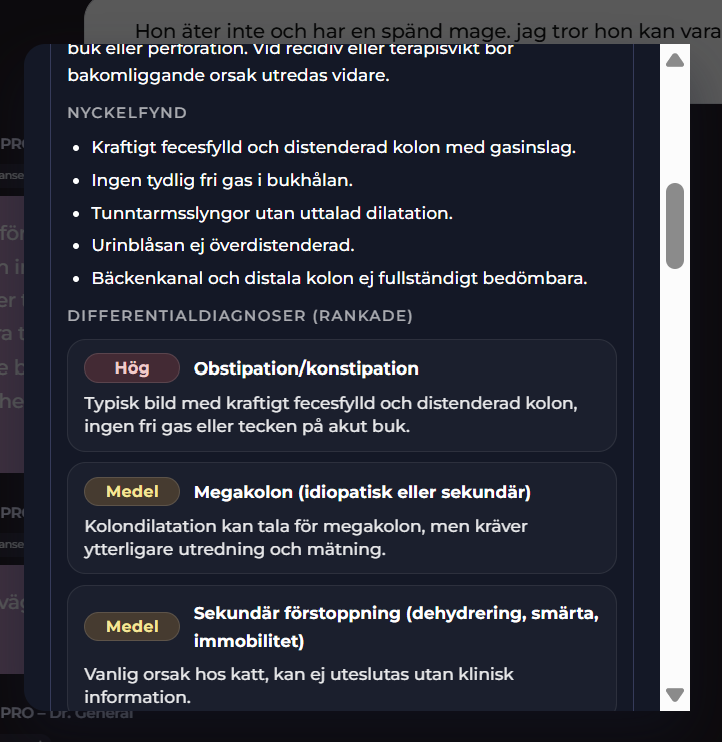

Radiologica Röntgentolk har utgått från chatt med din doktor som har en frågeställning som ska utredas. I detta exempel är det en katt som kan vara förstoppad. En komplett remiss har producerats. Remissens frågeställning tillsammans med röntgenbilder du kan ladda upp kommer att tolkas och generera ett remissvar.

Radiologica - Komplett remisssvar

I Visuella fynd (Stetoskåpet) finner du det kompletta remisssvaret. I remisssvaret kan du du titta på den strukturerade labrapporten samt läsa Labora´s svar på frågeställningen. Labora kommer svara både övergripande och i detalj för de enskilda biomarkörerna smat ge en rekommendation till din chatt AI doktor.